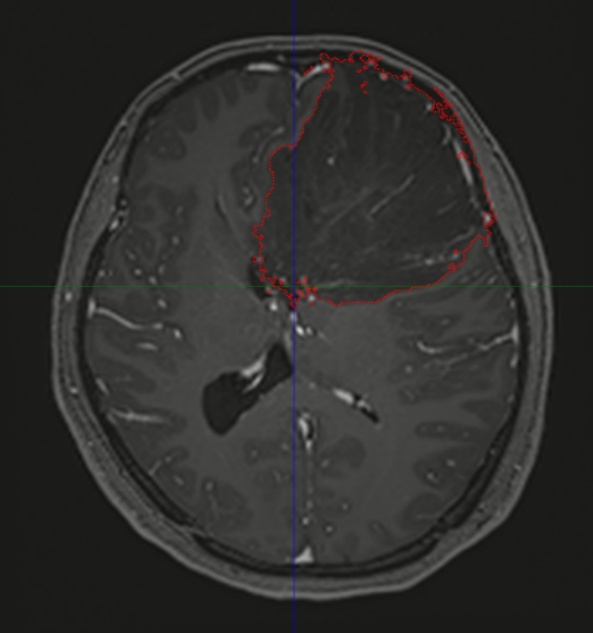

▲图中所示红色区域为肿瘤